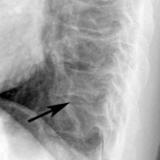

Bronch Cyst 1

arrow